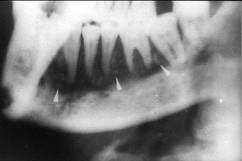

问题 慢性中央性颌骨骨髓炎的治疗应 ( )

选项 A.切开引流 B.及早拔除病灶牙 C.大剂量抗生素控制感染 D.全身支持疗法 E.死骨刮除、病灶牙拔除

答案 E